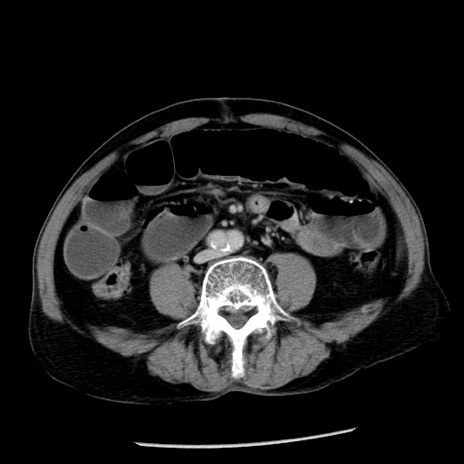

冠状断像

【症例】80歳代男性

【主訴】嘔吐

【現病歴】昨晩2回嘔吐あり、今朝になっても嘔吐あり。来院。

【既往歴】胃潰瘍

【身体所見】意識清明、BT 37.6℃、BP 166/95mmHg、HR 100bpm、SpO2 97%、腹部:平坦・軟、腸蠕動音聴取良好、圧痛なし。

【データ】WBC 21900、CRP 1.46